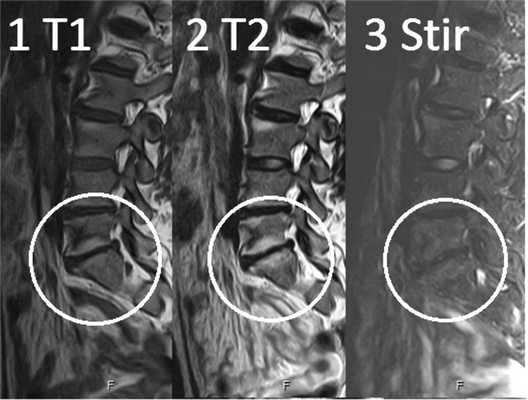

Изменения сигнала по типу MCh2 характеризуются гиперинтенсивным сигналом на T1- и Т2-ВИ и обусловлены жировой дегенерацией костного мозга (рис. 2). Гистопатологический анализ демонстрирует разрушение КПП и образование грануляционной ткани без гиперваскуляризации, замену костного мозга жировой тканью [2, 12].

Рис. 2. Изменения на МРТ по типу MCh2. 1 — гиперинтенсивный сигнал на T1-ВИ; 2 — гиперинтенсивный сигнал на Т2-ВИ; 3 — гипоинтенсивный сигнал в режиме подавления сигнала от жира (STIR).